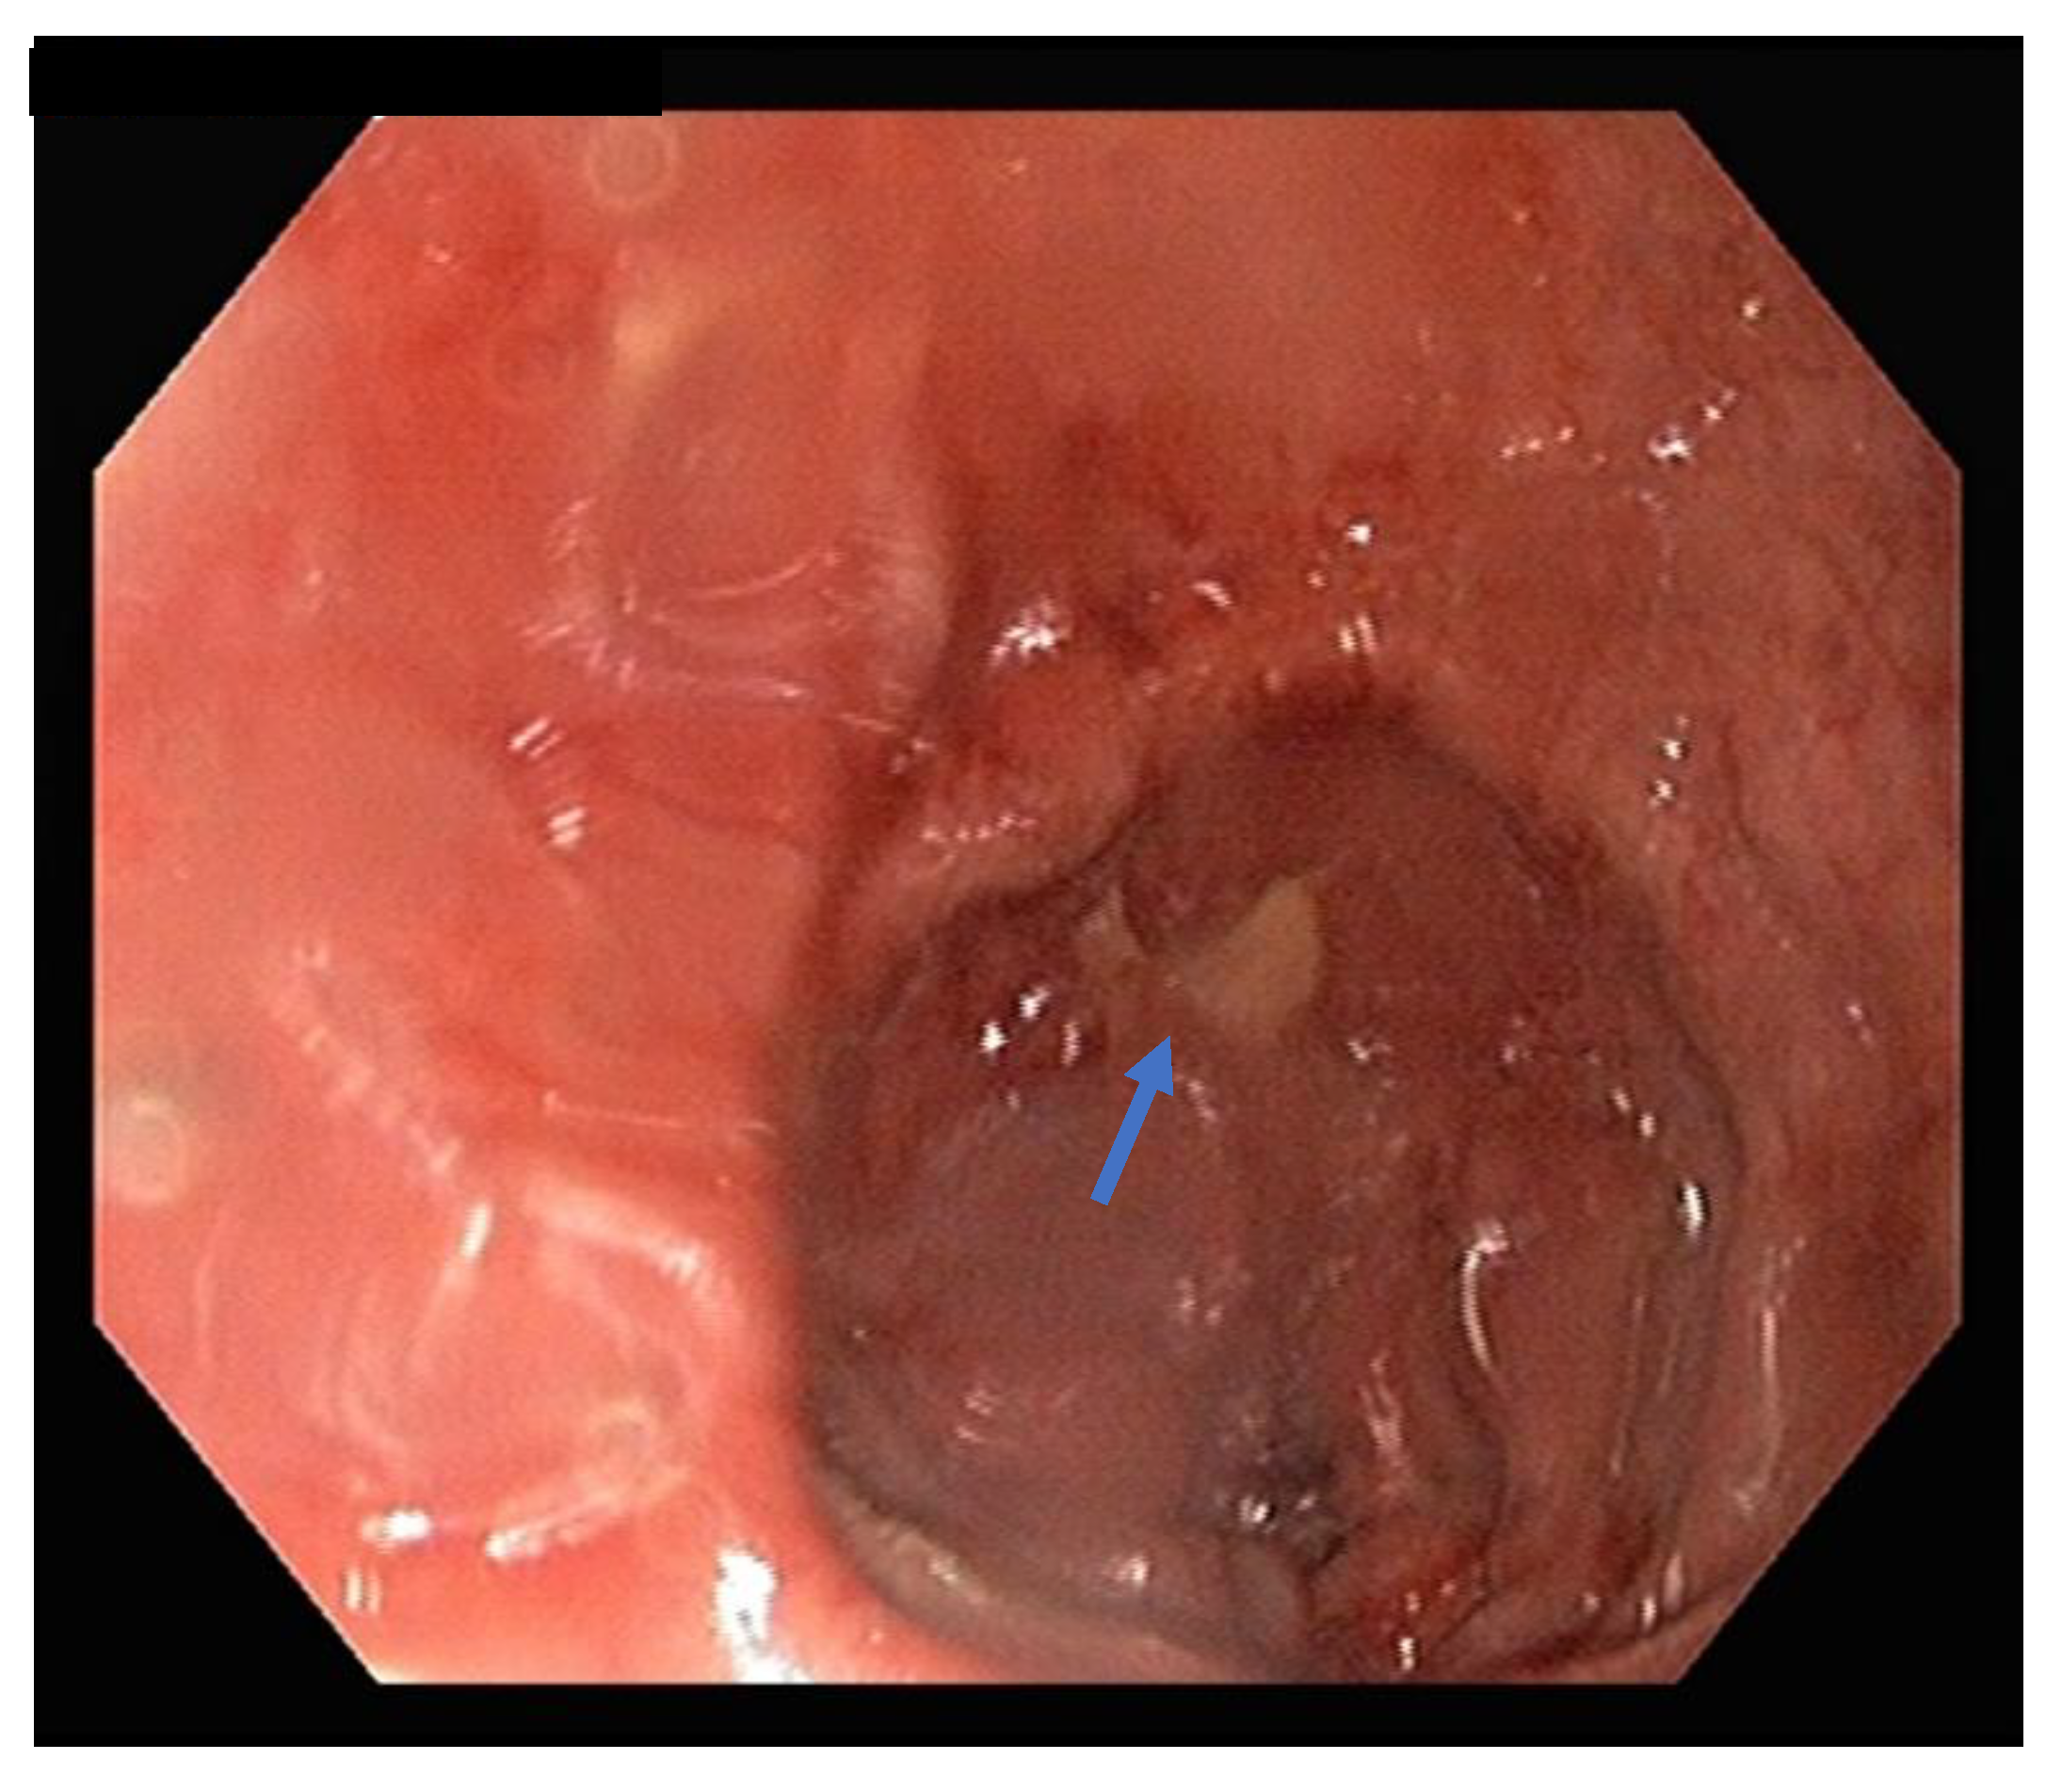

2.2. Treatment

2.3. Surgery